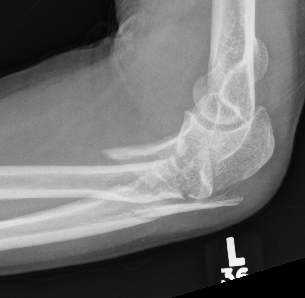

Elbow dislocation + olecranon fracture + radial head/neck fracture +/- coronoid fracture

Complex proximal ulna fracture with radial head replacement subluxation